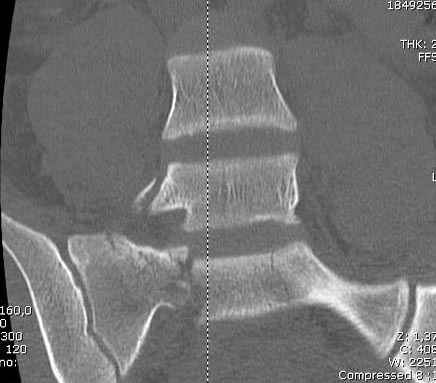

Здесь слайды случая больного с политравмой, включающей сегментарный перелом бедра и повреждение таза с нарушением тазового кольца, разрыв симфиза и перелома крестца зон 2 и 3.

На множественных слайдах важные моменты операции. Хотел бы подчеркнуть, как важно иметь возможности всех необходимых ренгенограмм, включая компютерную томографию и стандартных внутритазовых рентгенограмм (инлет и оутлет).